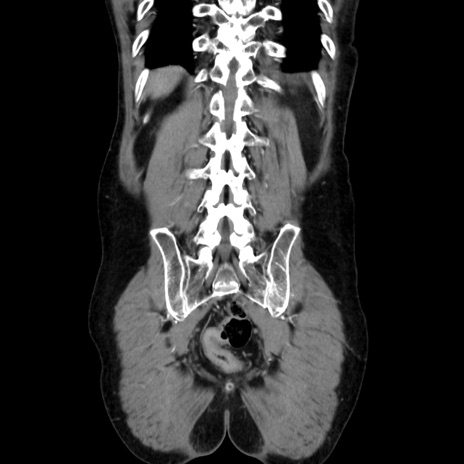

症例37(冠状断像)

【症例】40歳代 男性

【主訴】腹痛

【現病歴】4時間ほど前に電車に乗車中に臍部上より腹痛出現。徐々に増悪し起立困難となり、救急外来受診。生ものは数日食べていない。今朝お雑煮を食べた。

【身体所見】BT 36.8℃、BP 117/84mmHg、HR 91/min、SpO2 97%、苦悶様、腹部:臍上部広範囲圧痛あり、反跳痛±

【データ】WBC 8100、CRP 0.03